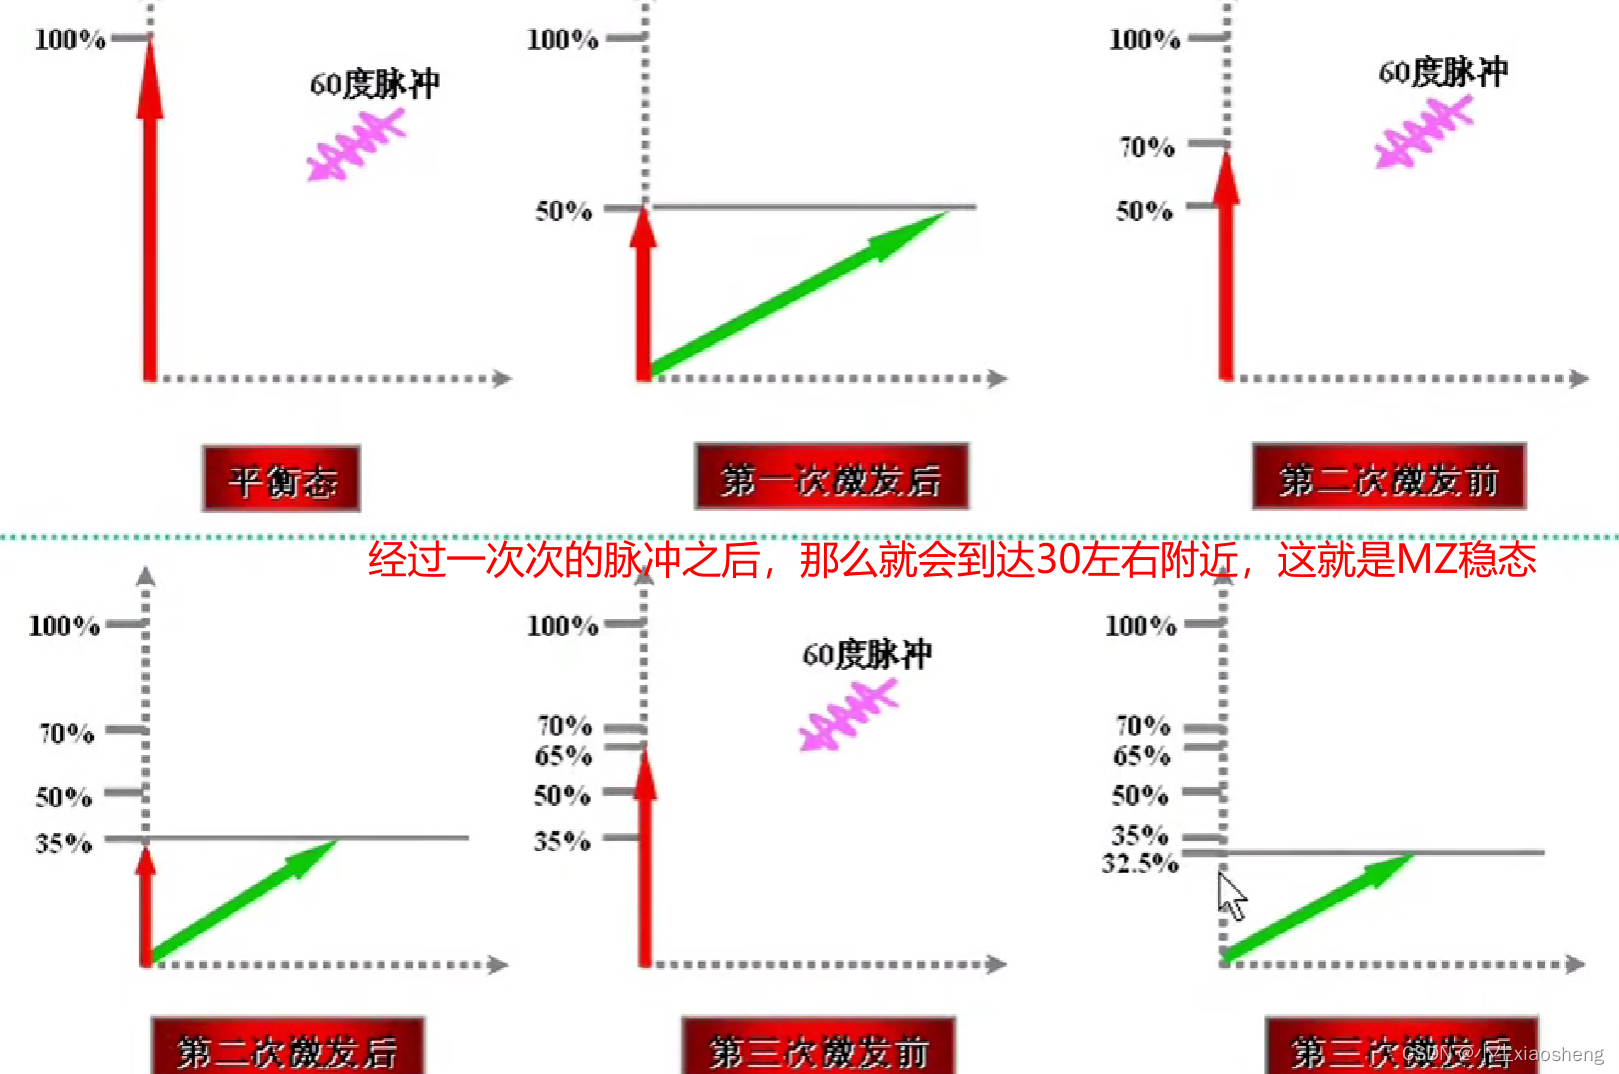

GRE序列中的稳态:流入的和流出的量是一样的,那么容器中的数据一直都是一样的。